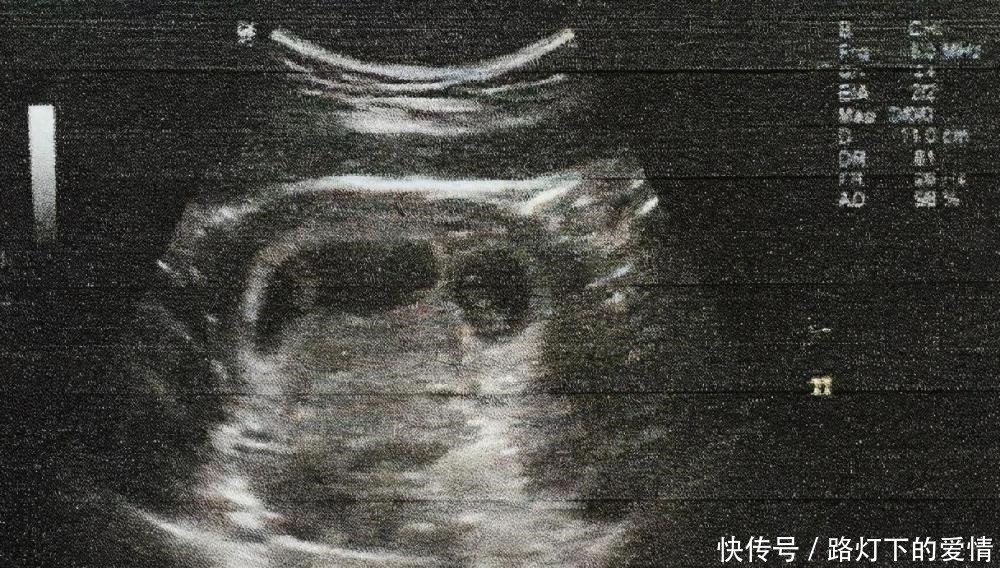

怀孕5-6周的孕妇已经可以通过B超检查看到胎囊,这就是最早的胚胎,还不是一个成型的胎儿。 在这个时间段能够看到胚胎长出了胎芽,同时胎心管也有轻微的跳动,这说明胎儿已经有心跳的表现。 如果出现胎心、胎芽并且情况正常,说明胎儿的发育良好。 但有的孕妇在有正常的胎心后还是会发生胎停,所以,即便是出现胎心,仍然不敢掉以轻心。至少要等到孕后12周也就是3个月后,情况才会稳定下来。